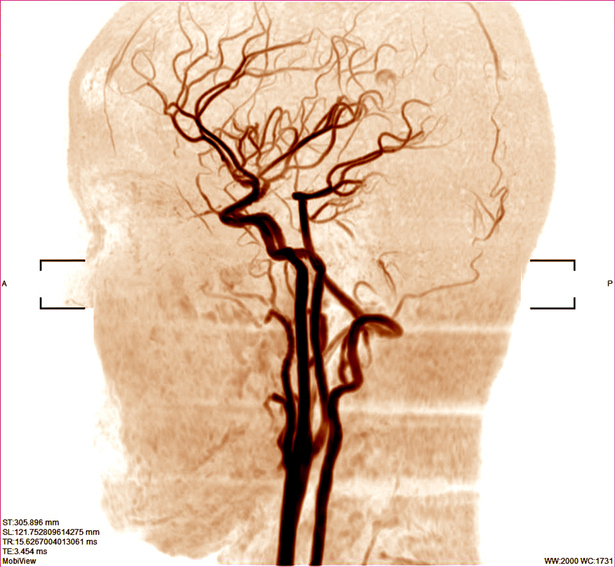

'비파열성 뇌동맥류'는 뇌혈관 벽이 약해지고 부풀어 오른 병변으로, 뇌출혈을 일으킬 수 있는 잠재적 위험이 있는 질환이다. 그런데 자신에게 이 질환이 있다는 것을 알게 된 환자는 그렇지 않은 사람보다 정신질환을 진단받을 가능성이 10% 더 높은 것으로 나타났다. 특히 40세 미만의 '젊은' 환자에게서 정신건강 문제 위험이 더 크다는 연구 결과가 발표됐다. 뇌혈관이 언제 터질지 모른다는 불안감에서다.

그동안 비파열성 뇌동맥류 진단을 받은 환자들의 스트레스와 불안 패턴을 관찰한 연구는 있었지만, 대규모 인구집단을 대상으로 진단 이후 정신건강 문제의 위험성을 추정한 건 이번 연구가 처음이다. 연구 결과는 비파열성 뇌동맥류로 진단받은 후 수술 치료 없이 모니터링을 통해 추적관찰이 이뤄지는 경우, 우울증·불안증 등 정신질환을 앓을 확률이 높다는 것을 시사한다.

공동 교신저자인 이대목동병원 신경외과 양나래 교수는 "뇌동맥류 진단 후 수술적 치료를 받지 않고, 영상 검사를 통해 추적 관찰하는 환자 중 상당수가 언제라도 치명적인 뇌출혈이 일어날 수 있다는 공포감에 두려움과 불안을 느끼는 것을 진료 중 경험했다"며 "뇌동맥류를 치료하는 의사들은 비파열성 뇌동맥류 진단 자체가 환자의 심리적 부담을 가중해 정신질환에 기여할 수 있다는 점을 치료 과정에서 고려해야 한다"고 설명했다.